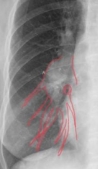

(一)X线平片心脏、大血管的正常投影

1后前位(正位)重点强调后前位胸片上心影轮廓的构成

IMG_29752021-06-07 14:34:48.7150002021-06-07 14:30:43.795000

1心右缘分为两段

上段为主动脉与上腔静脉的总投影

下段为右心房构成

2心左缘分为三段

上段为主动脉结

中段为肺动脉主干

下段由左心室构成